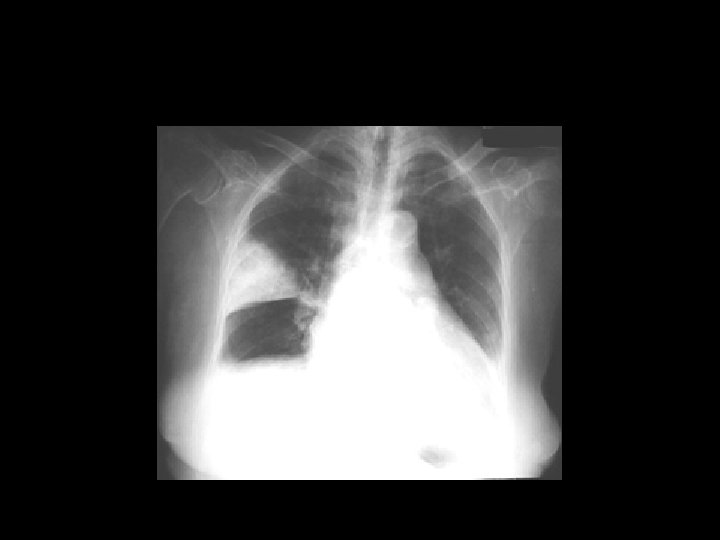

Pneumonia History: - Cough - Shortness of Breath - Fever - Sputum Examination: - Dullness - ↑ Vocal fremitus - Bronchial Breathing - Crackles Treatment: - Oxygen - Antibiotics